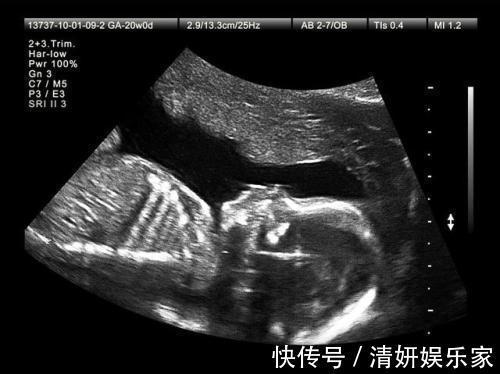

3、第三次产检时间:孕17-20周项目:复查血常规、尿常规、宫高、腹围、胎心、血压、体重等例行项目和四维彩超胎儿畸形筛查。注意:不需要空腹,这次检查主要是常规例检,以B超和彩超为主。